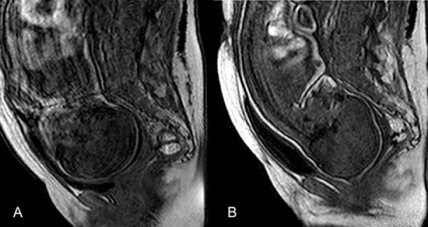

Группа американских и французских ученых провела сканирование магнитно-резонансным томографом женщин, находившихся на втором периоде родов, и проследила, как в ходе этого процесса меняется череп ребенка. Работа опубликована в журнале PLOS One.

О том, что череп младенца деформируется во время родов, врачи знали до этого, но сейчас за этим процессом они проследили при помощи трехмерной магнитно-резонансной томографии (3D MRI). Всего они обследовали 27 женщин, находившихся в предродовом состоянии. Только семь из них прошли сканирование во время второго периода родов, когда шейка матки полностью открывается и начинается выход плода. Процедура длилась не более десяти минут.

Результаты сканирования поразили исследователей, так как деформация черепа и мозга ребенка происходила во всех семи случаях и, по-видимому, является частью нормальных родов. Пять детей вышли естественным путем, в двух случаях пришлось применить кесарево сечение.

Ученые пришли к выводу, что изменение формы черепа ребенка при родах — часть нормального процесса, но чрезмерная деформация может быть опасна. В первых пяти случаях, когда младенцы вышли без хирургического вмешательства, форма головы быстро возвращалась к нормальной — той, которая наблюдалась в утробе. Двум другим потребовалось на это гораздо больше времени — до десяти минут. Шесть из семи младенцев получили высокие оценки по шкале Апгар (система быстрой оценки новорожденных), а последний, который вышел благодаря кесаревому сечению, набрал необходимые баллы только к десятой минуте жизни.